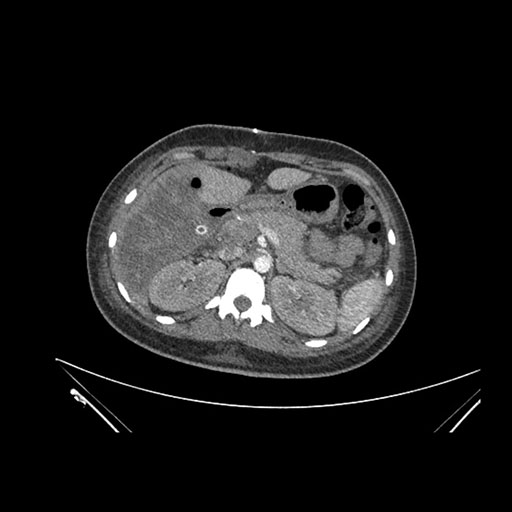

Axial Arterial

Axial Venous